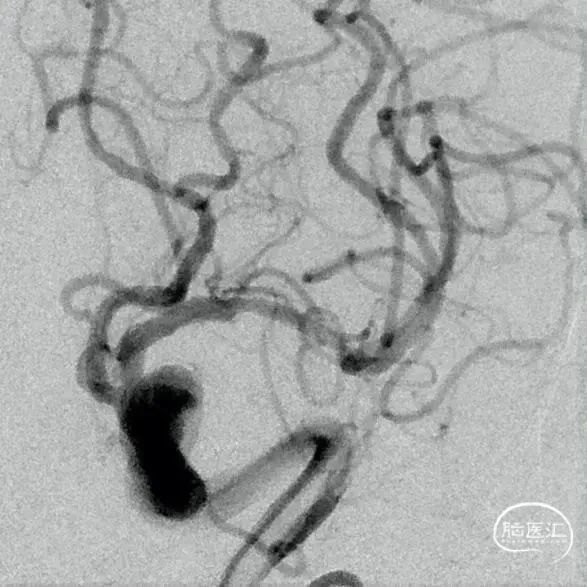

左侧颈内动脉造影显示左侧大脑中动脉M1段重度狭窄。

支架完全释放后造影显示支架打开良好、贴壁可。

术后造影显示左侧大脑中动脉血流较前改善,远端血管无缺失,残余狭窄约20%。